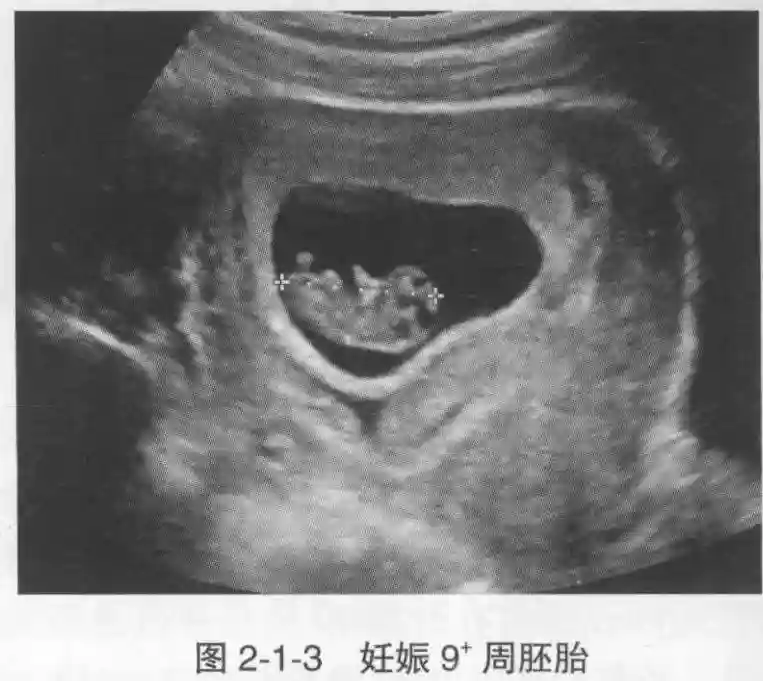

3??胚胎:胚胎通常在6-7周时可以为超声显示,起初为胎芽,表现为卵黄囊一侧局部组织增厚,达到1 -2 mm 时才有可能为超声测量出来。达4-5mm时可见胎心搏动,相应孕周为6-6.5周,妊娠囊大小为13-18mm。胚芽长度≥7㎜时仍未见心管搏动,提示胚胎停止发育。胚胎的出现和妊娠囊直径的关系:妊娠囊直径> 16 mm 时,经阴道超声应显示胚胎。妊娠囊直径> 25 mm 时,经腹超声均应显示胚胎。

4??胎心搏动:胎心搏动通常出现于6-6.5周,胚胎在4- 5mm就应该显示胎心搏动。

5??羊膜:早孕期羊膜囊菲薄,超声常不能显示。孕7周以后加大增益或者用高频超声可以显示羊膜。羊膜囊位于绒毛膜内,胚胎位于羊膜囊内。随着胚胎增长,羊水增多,羊膜囊增大,孕12-16周时,羊膜与绒毛膜全部融合,胚外体腔消失。宫腔线一侧内膜内一圆形增强回声区,中央有小囊状液性暗区,宫腔线局部突起变形,称蜕膜内征,用于判断早早孕。